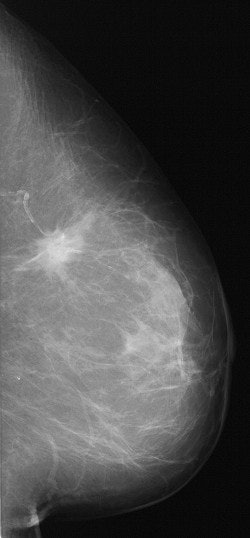

![]() ![]() |

DSPM images acquired on the Mammomat 3000 Nova, including zoom (middle) and spot magnification (below). Images courtesy of Dr. Wolfgang Matzek.